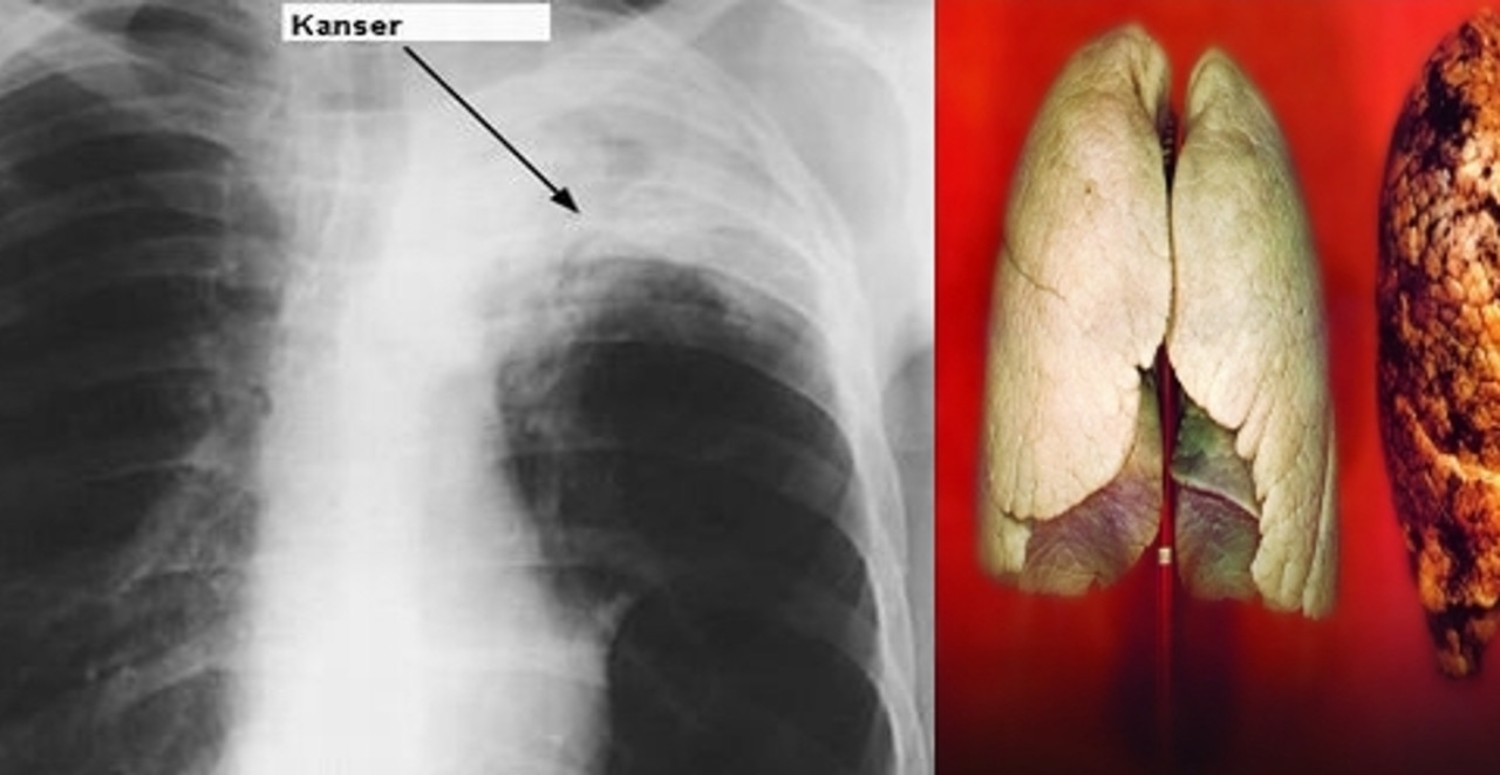

Türkiye, akciğer kanseri görülme sıklığı açısından erkeklerde dünya birincisi, her iki cinste ise 5'inci sırada yer alıyor. Bu hastalık, yılda yaklaşık 20 bin kişinin hayatını kaybetmesine neden oluyor. Akciğer kanserinin en büyük sebebi ise sigara. Uzmanlar, sigara içenlerin bu alışkanlıklarından bir an önce vazgeçmeleri gerektiğini vurguluyor. Peki akciğer kanserinin belirtileri neler, tedavisi var mı? Detaylarda...

Akciğer kanserinin erken teşhis edilmesi, hastalıksız ve uzun bir yaşam süresi sağlamak için çok önemli. Bu nedenle, akciğer kanserinin belirtilerine dikkat etmek gerekiyor. İşte akciğer kanserinin belirtileri:

Akciğer kanseri tedavisi ise hastalığın evresine ve hastanın durumuna göre değişiyor. Erken evrede yakalanan hastalarda, ameliyat ile kanserli akciğer dokusunun çıkarılması en etkili tedavi yöntemi olarak gösteriliyor.

İleri evre hastalarda ise kemoterapi, radyoterapi ve immünoterapi gibi tedavi seçenekleri uygulanabiliyor.